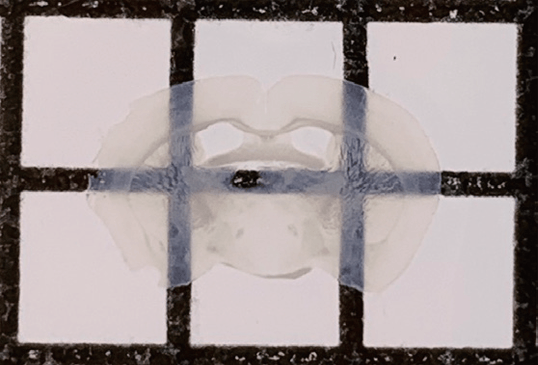

original brain 하이브리드 겔 후

조직은 지질로 이루어진 세포막을 불투명하게 보이게 하는데, 제가 개발한 기술은 세포막에 있는 지질을 제거해서 투명하게 만드는 원리입니다. 세포막을 그대로 제거하면 조직이 무너지므로 전처리 과정에서 하이브리드 겔을 침투시켜 젤화한 다음, 세포막에 있는 지질을 제거하면 조직이 투명해지지만 위치나 구조는 그대로 유지되는 원리입니다.